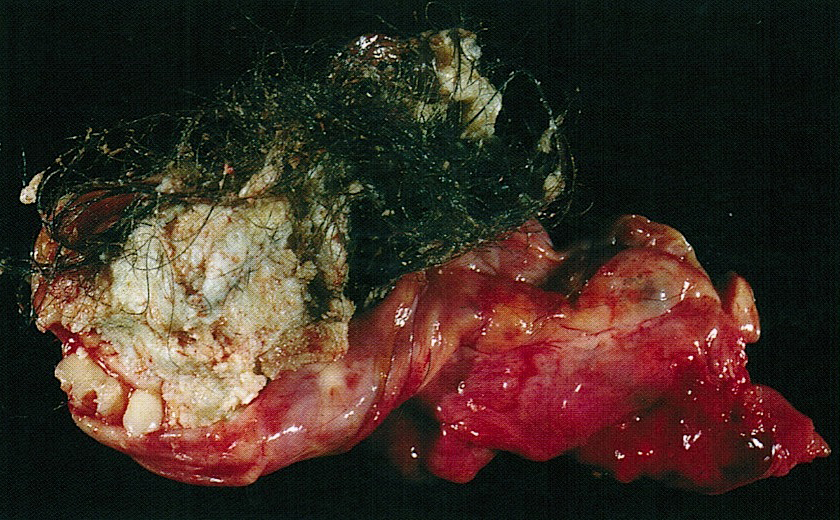

Gross description

- Smooth cyst that may contain hair, teeth, cartilage, bone or sebaceous material

- Generally < 10 cm

- Raised protuberance in cyst wall (Rokitansky nodule)

- Reference: StatPearls: Cystic Teratoma [Accessed 29 July 2021]

Gross images

D. Mature teratoma. The photo shows a mass with yellow sebaceous material and hair. In a 19 year old woman, this most likely represents a mature teratoma. Mature teratomas are the most common ovarian tumor and are especially common in women of reproductive age.